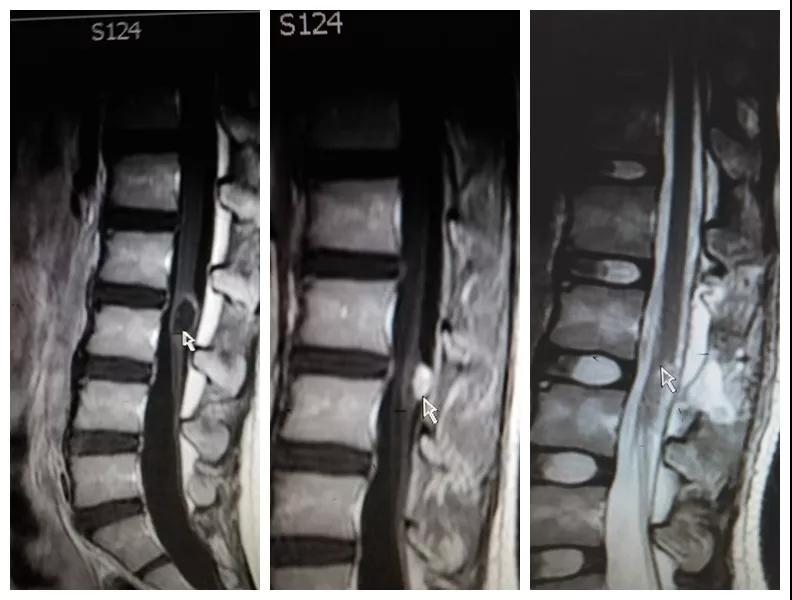

2018年8月,孩子母亲带着一线希望慕名找到91论坛 神经外科王占尧主任医师。王医生通过详细询问病史、查体、完善相关检查后,明确诊断患者为腰3椎管脊髓内畸胎瘤、硬脊膜外脂肪瘤、脊髓栓系综合症、骶尾部皮毛窦。王占尧耐心与家属沟通病情及手术方式,因手术难度大费用较高患者家属有些犹豫,随后又到西安多家医院咨询,最终选择在中心医院神经外科手术。因患者椎管处有不同部位的四个病变,还伴脊髓内畸胎瘤,分几次手术安全性高但是存在再手术医疗费用高、住院时间长耽误孩子上学等问题,如果选择一次手术切除则存在手术时间长、肿瘤是否能最大限度的全切、污染手术与清洁手术同时进行等系列问题。王占尧主任医师组织医疗团队反复讨论患者病情、斟酌手术方式、评估手术风险、制定详细的手术方案,最终决定在全麻下一次手术为患者同时切除四个病变部位。孩子的父母是一辈子面朝黄土背朝天的农民,面对术前谈话时主管医生提到的种种风险,他们不能完全理解,只是落泪重复:“孩子是我两的希望,我们就把孩子交给你了王大夫!”王占尧正是承受着一旦手术失败,孩子可能原有症状加重、甚至终身大小便失禁、双下肢瘫痪的压力,带着孩子父母沉甸甸的希望走进手术室。

手术很成功。术后孩子恢复非常好,未出现并发症,复查磁共振肿瘤切除干净,大小便失禁症状较术前明显好转,腰部疼痛也得到了缓解,目前已痊愈出院。